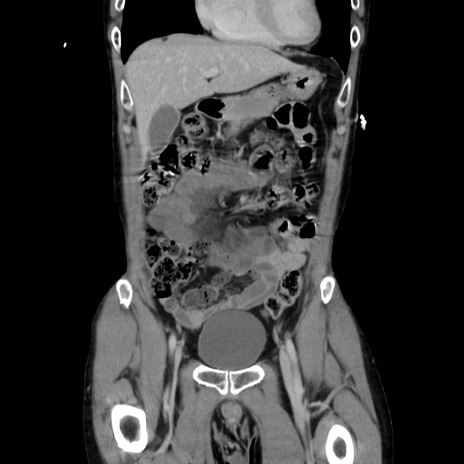

横断像

【症例】40歳代 男性

【主訴】腹痛

【現病歴】4時間ほど前に電車に乗車中に臍部上より腹痛出現。徐々に増悪し起立困難となり、救急外来受診。生ものは数日食べていない。今朝お雑煮を食べた。

【身体所見】BT 36.8℃、BP 117/84mmHg、HR 91/min、SpO2 97%、苦悶様、腹部:臍上部広範囲圧痛あり、反跳痛±

【データ】WBC 8100、CRP 0.03